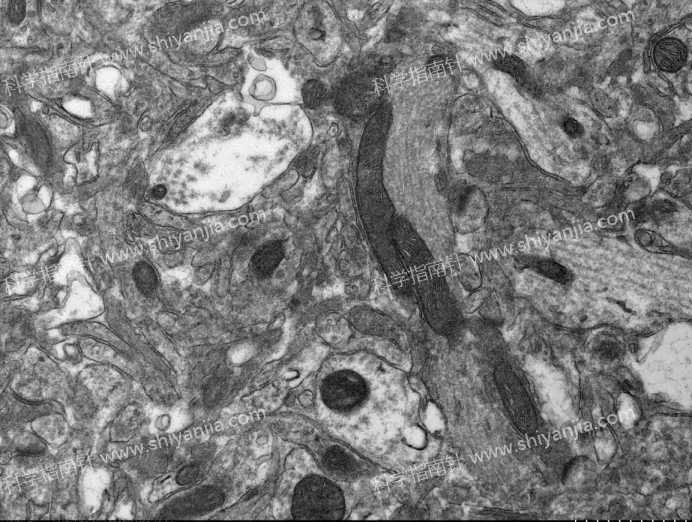

灌流组

2.2 分钟是黄金取材窗口:灌流组 2 分钟内取材,样本超微结构无显著退化,膜结构清晰、细胞器形态完好,是兼顾操作可行性与样本质量的最佳时间。

灌流组

3.5 分钟是损伤临界值:无论是否灌流,取材时间超过 5 分钟,样本都会出现明显的缺氧损伤,空泡形成、线粒体肿胀等问题频发,实验可重复性大幅降低。

灌流组

4.不同结构耐受度不同:髓鞘和突触对短时间缺血具有相对耐受性,受灌注处理和短时间取材延迟的影响较小。